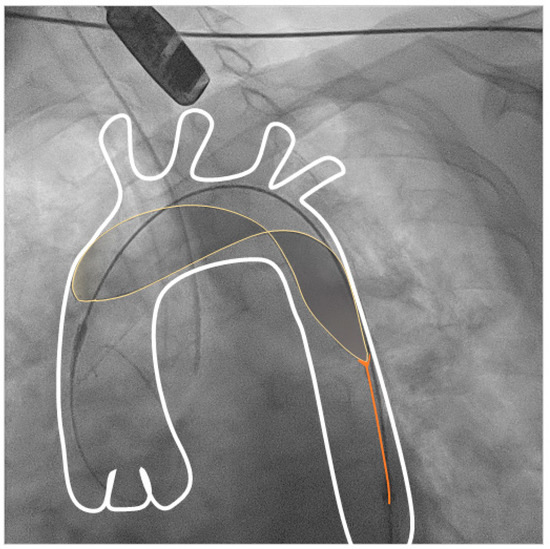

2.2.2. Triguard 3 Device

2.2.4. VT Ablation Procedure

4.3. Technical Aspects